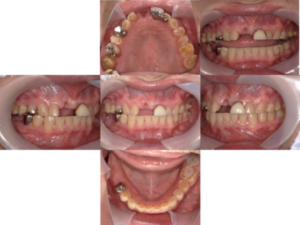

では、初診時の口腔内写真とレントゲン写真です。

初診時

右上の奥歯を圧下した後の口腔内写真です。

右下の奥歯のインプラントに仮り歯を装着した後の口腔内写真です。

治療終了後の口腔内写真とレントゲン写真を示します。

治療終了後